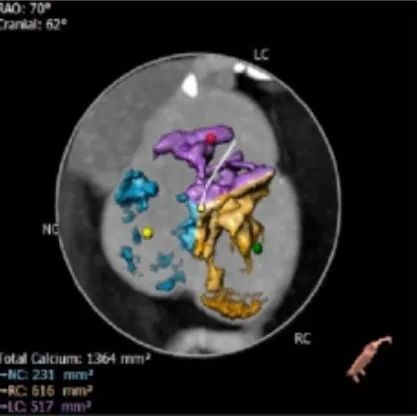

钙化分布

HU542钙化积分1364mm³